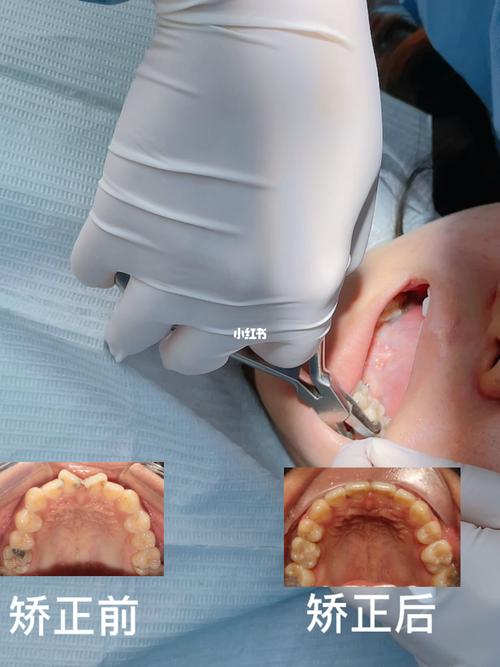

扭转牙是指在牙列中,牙齿围绕其长轴发生异常旋转,导致牙冠与牙根方向不一致,是常见的牙齿错畸形类型之一,临床上多见于前牙,尤其是上颌侧切牙和下颌前牙,表现为牙冠向唇侧或舌侧旋转,甚至呈“拧麻花”状,不仅影响面部美观,还可能造成咬合功能障碍、牙周组织健康受损,以及发音、心理等问题,随着正畸技术的发展,扭转牙的矫正已形成系统化方案,通过精准的力学控制可有效改善牙齿位置,恢复口腔健康与功能。

传统矫正需分阶段更换弓丝:先用镍钛圆丝排齐牙列,再用不锈钢方丝配合“扭转簧”“链状皮圈”等附件施加旋转力,通过“旋转-控根”两步法将牙冠与牙根同步调整;隐形矫正则需每1-2周更换一副牙套,每副牙套上设计“附件”(如小凸点)增强牙齿抓持力,计算机模拟确保每一步旋转角度在安全范围内;舌侧矫正因托槽位置特殊,需个性化定制弓丝与托槽,通过“三维力系统”精细控制牙齿移动。

第三阶段:保持阶段